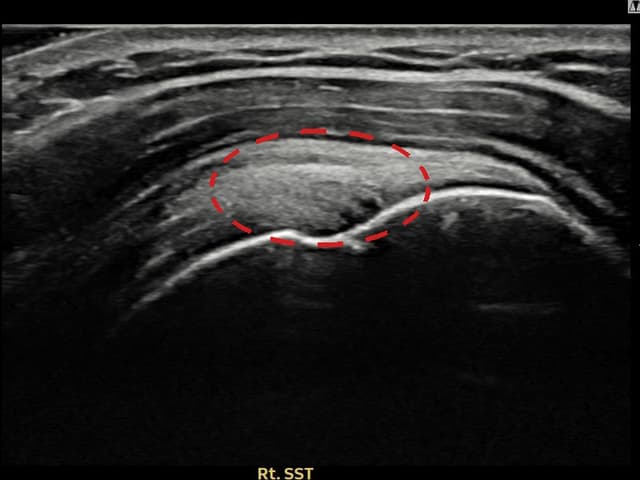

[촬영시기:22.09.19~22.12.09]

[어깨인대 축소봉합술] 우측 어깨 통증이 수개월간 지속되어 내원하셨습니다.